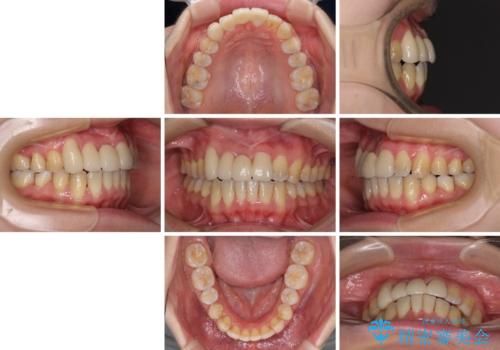

転んで前歯が欠けた 折れた前歯をきっかけに矯正治療で歯列をきれいに整える

- 転倒により前歯の一部が欠けてしまったとのことで来院された患者様です。

元々歯並びが気になっていたとのことで、前歯の治療を行うことを契機に矯正治療も行うこととしました。

本来であれば積極的に小臼歯を抜歯して口元を下げても良いのですが、前歯を1本抜歯しないといけなくなったため、非抜歯矯正をインビザラインを用いて行うこととしました。

補助装置により上顎歯列を遠心移動させたため、非抜歯でしたが口元の突出感をある程度改善させることができました。

欠けてしまった前歯もオールセラミッククラウンにて自然に補綴することができました。